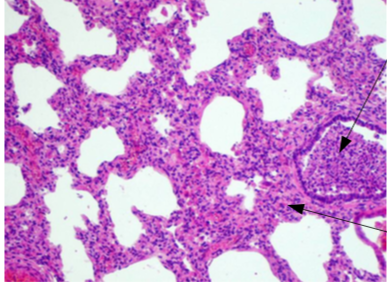

Slide:

Describe the appearance of the

Normal area and Inflamed area:

Bronchopneumonia

Bronchi filled by pus (inflammation start in bronchi, then involves other areas) (neutrophils, cellular debris).

Causes: Patients with long term diseases